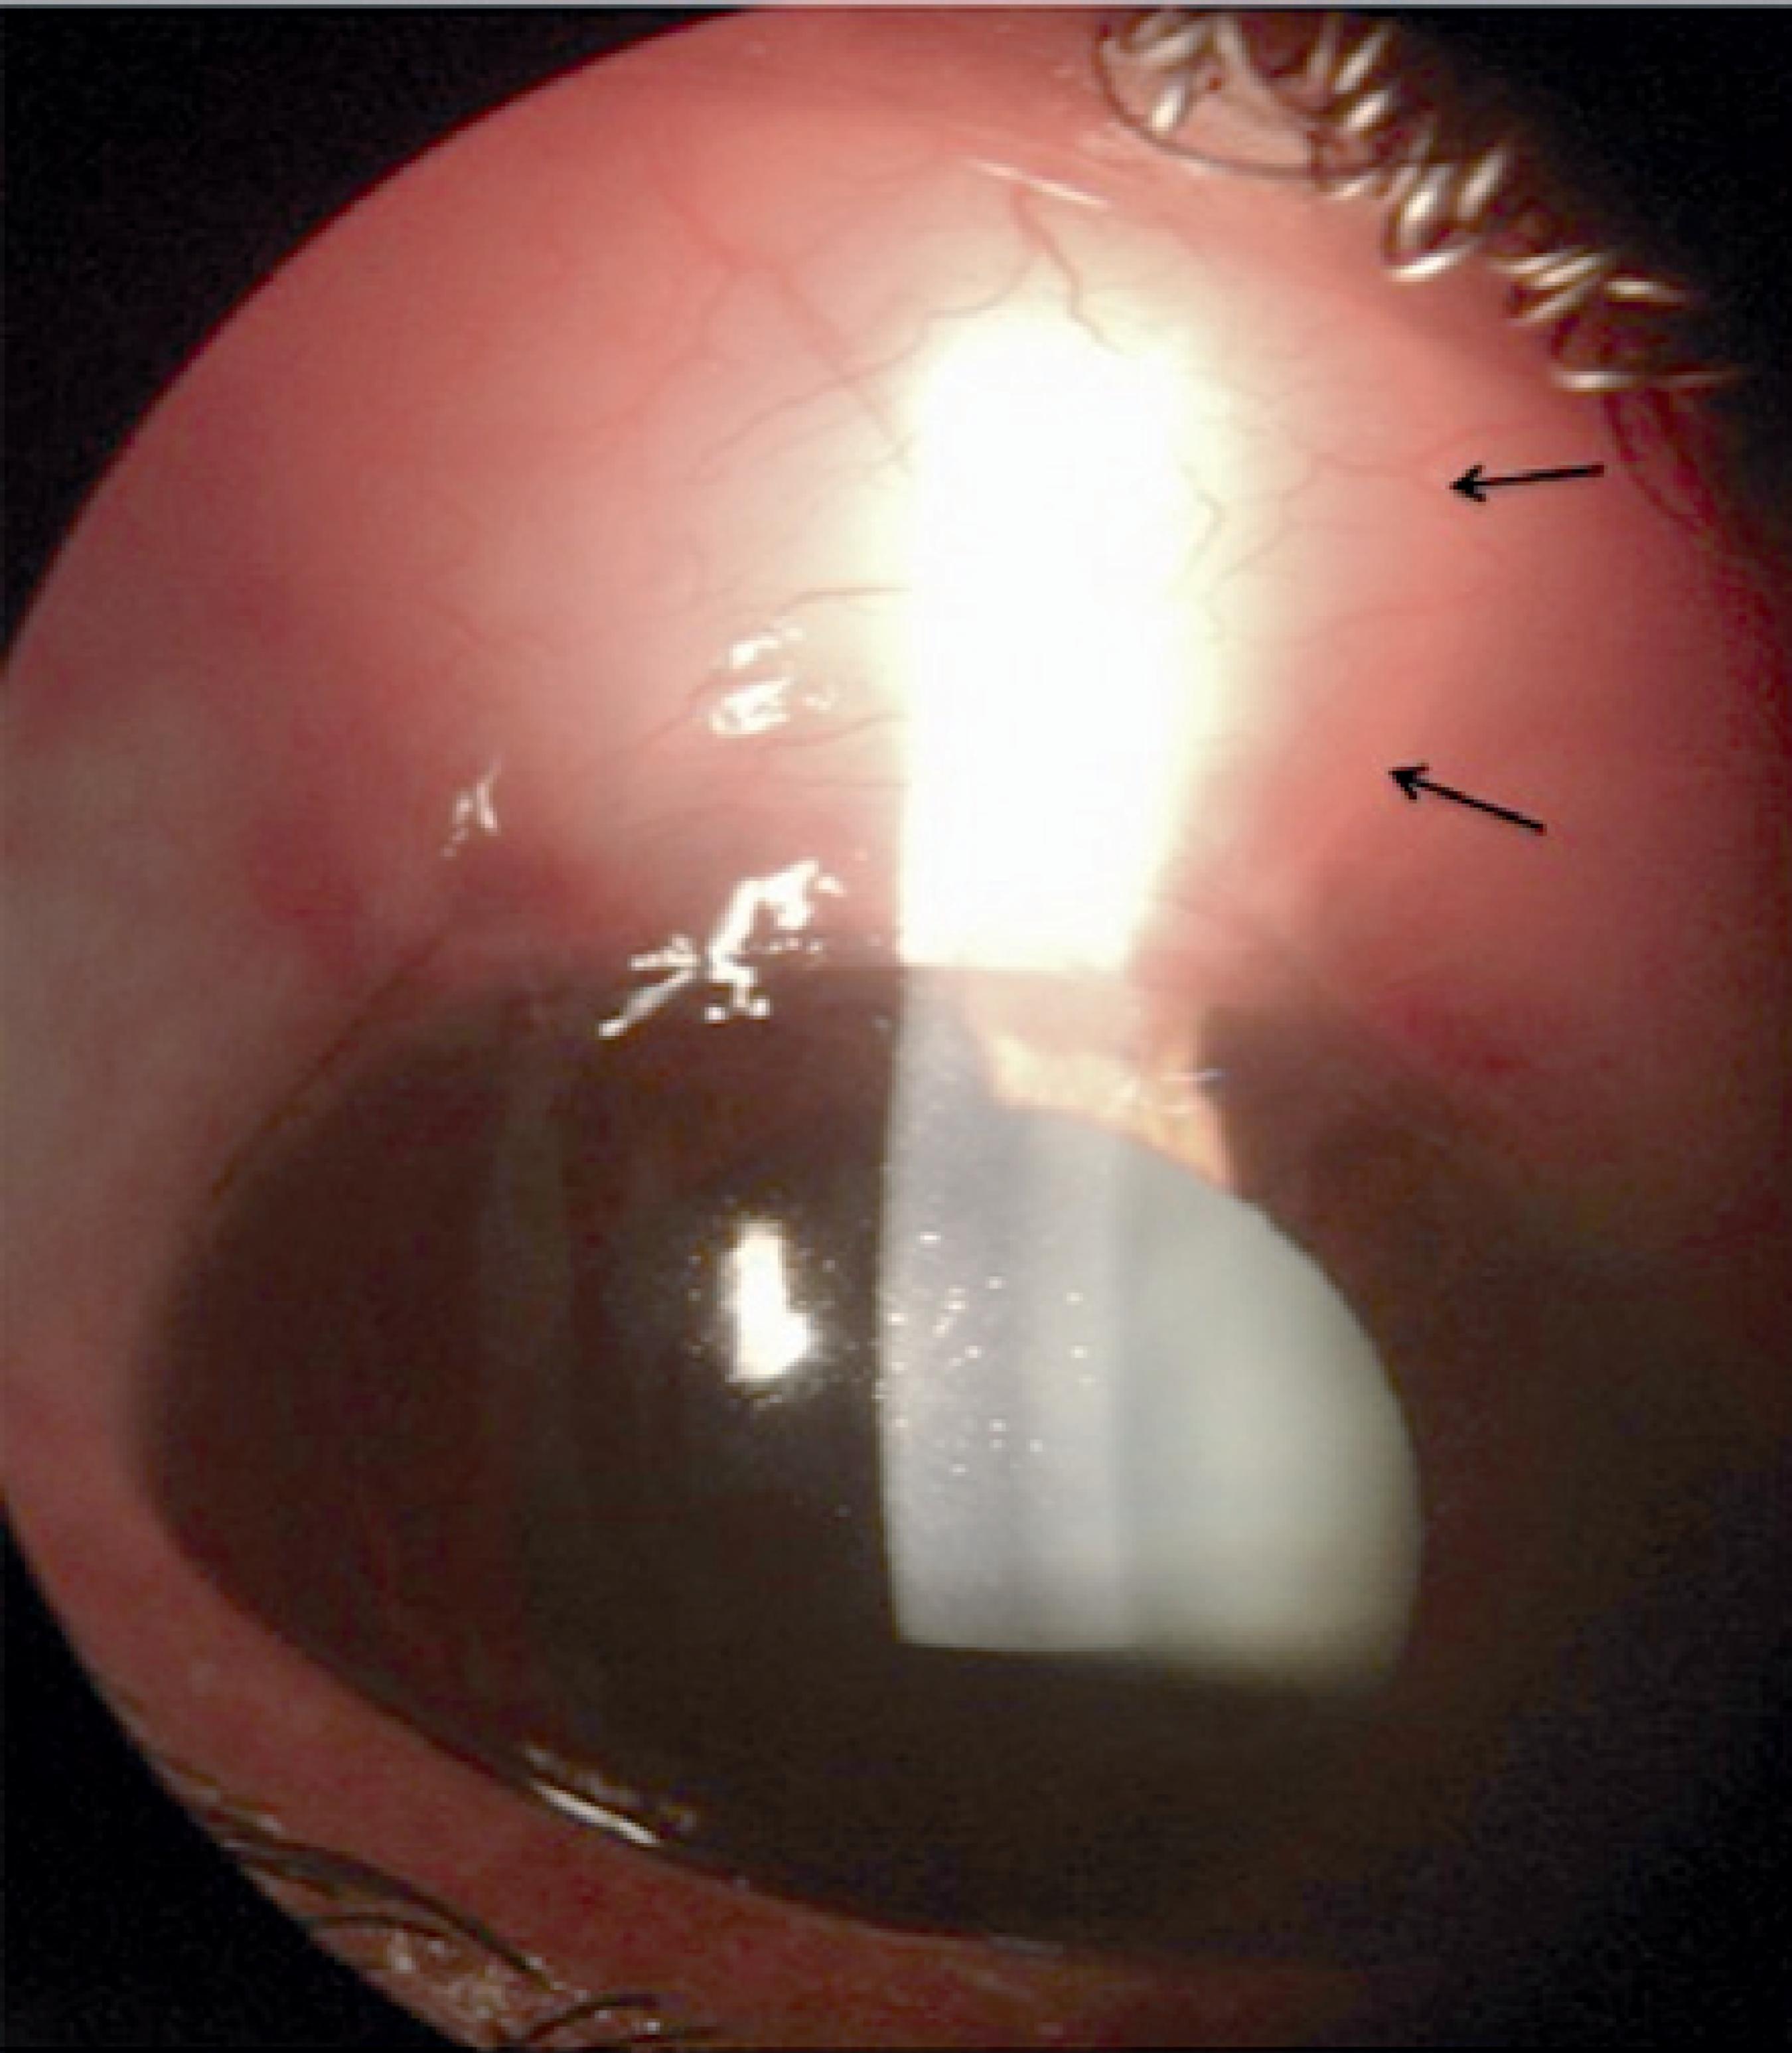

HPLC detected bevacizumab in BMM at a mean retention time of 6.98 min across the five samples evaluated at 72 h (mean of 75.1% of free drug), close to the well-defined peak of free bevacizumab at 7.01 min (Figure 1)(5) BMM could be observed in the bleb areas of all patients during the first week (Figure 2). The blebs remained expanded with the hyaline material, but the liquid interface of aqueous humor could not be visualized during the slit-lamp examination.

We could not determine whether there was a synergistic effect between bevacizumab and methylcellulose in this study, but we believe that BMM may act as a slow delivery system for bevacizumab to the subconjunctival space, particularly during the first week post-surgery. The artificial expansion of bleb volume with this viscoelastic product may also contribute additional benefits, primarily in the first phase of the healing process(7).